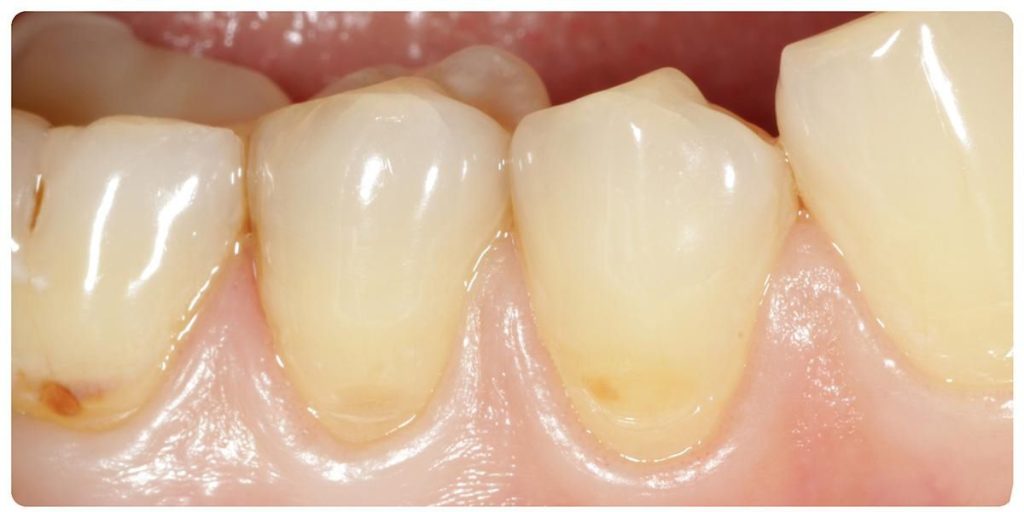

Dobrze przeprowadzony zabieg implantacji natychmiastowej daje efekty jak na pozostałych zdjęciach! Na każdym etapie leczenia mamy pełną kontrolę nad wszystkimi aspektami przyszłej odbudowy protetycznej – można powiedzieć, że zachowujemy to, co najtrudneijsze do odtworzenia, czyli kształt dziąseł.

Cytując Michała Mokijewskiego: „Pacjent przychodzi po idealny ząb, a nie po implant”.

Tylko implantacja natychmiastowa pozwala nam uzyskać taki efekt w zaledwie 3 wizyty.